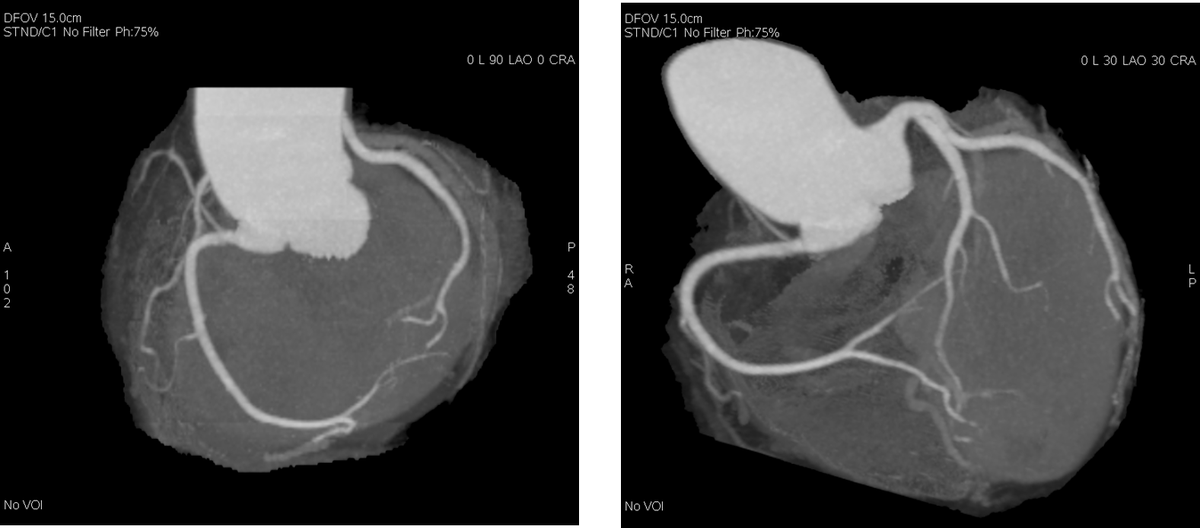

Называется он КТ-коронарография. Делается с контрастом, чтобы проверить проходимость сосудов сердца. Некоторые кардиологи называют его “золотым стандартом” диагностики ишемической болезни сердца.

Что он показал? У меня была почти на 70% закупорка одной из коронарных артерий.

«Вы были в 2 шагах от инфаркта. Любой стресс, и…», — сказал врач, показывая снимок.